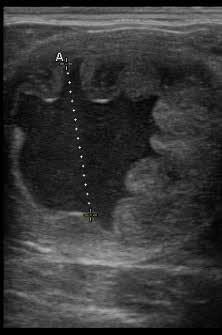

Intrauterine fluid Al images are courtesy of Rood & Riddle

Due to the minimal improvement with previous treatment, and the potential for biofilm and persistent infections given the chronicity of the case, the decision was made to use an inflammatory agent to stimulate the uterus to resolve the infection. Infusion of 500 mL kerosene into the uterus during late estrus occurred. Uterine lavage with LRS (3-5 L) was performed until the efflux was clear for the next 2 days.

Two weeks later, transrectal ultrasonography revealed a 50 mm follicle on the left ovary, a 30 mm follicle on the right ovary, uterine edema of 3, trace uterine fluid, an open cervix at 3, and 2 g ceftiofur (60mL volume in 0.9% sterile NaCL) was infused into the uterus.

A cervical laceration repair Transrectal ultrasound image of a uterus following infusion of 500mL of Kerosene. Image taken 18 hours after infusion. The uterine lumen is profiled where the hyperechoic line is outlining the endometrial folds. Day 7 Grade 2 embryo